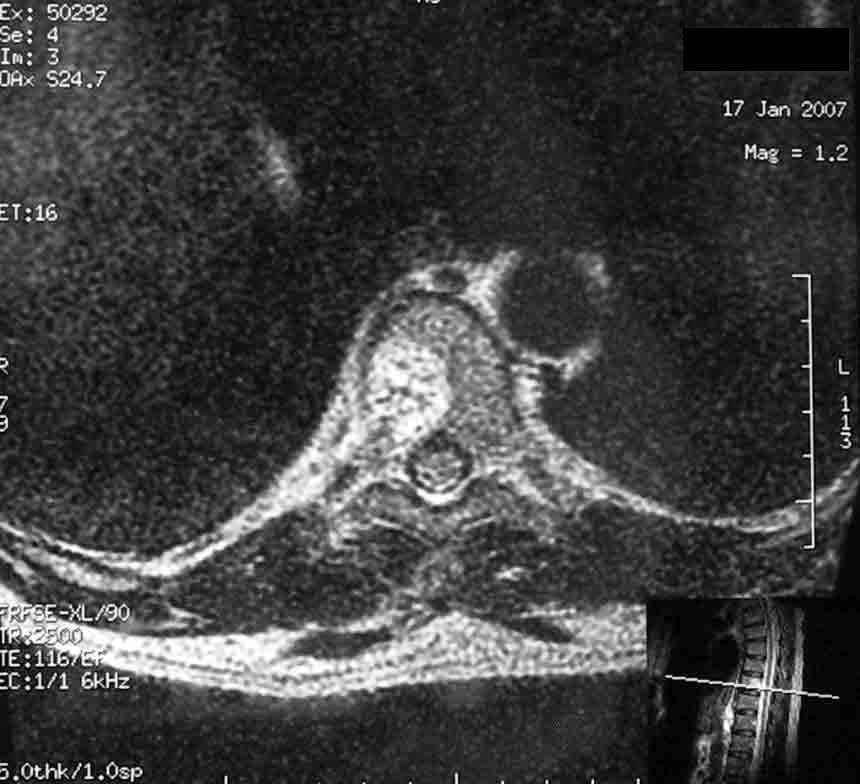

Уважаемые коллеги! У пациентки 50 лет, сотрудницы нашего центра проводили обследование по поводу хронических болей в поясничном и грудном отделе позвоночника.

Помимо распространённого остеохондроза и деформирующего спондилёза обнаружили гемангиому 1/2 тела Th-9 позвонка. Какова может быть тактика лечения гемангиомы? Локальной болезненности при пальпации 9-го грудного позвонка нет, боли носят распространённый характер, не привязаны к Th-9. С уважением, Мамонов Василий, ГНЦ РАМН.